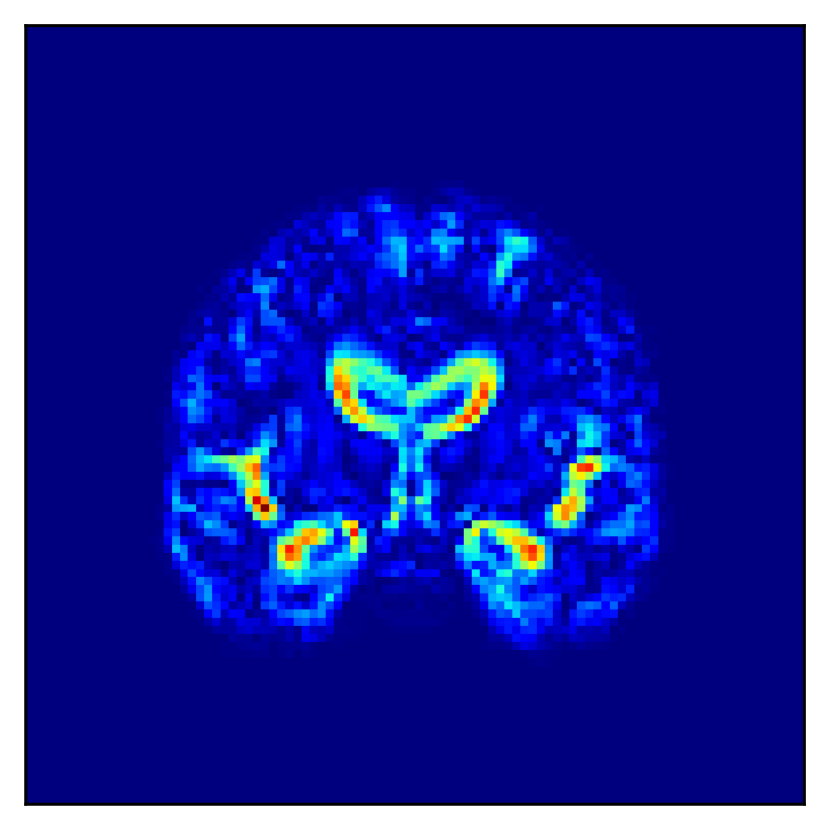

Refer to caption Refer to caption Refer to caption

(a) (b) (c)

Figure 5: Brain regions affected by the one dimension with the largest difference between the AD and CN conditions among the low-dimensional representation obtained. (a) naïve β𝛽\beta-VAE, (b) β𝛽\beta-VAE (TW), and (c) Loc-VAE.

Fig. 5 shows the difference in the reconstructed images (the coronal, sagittal, transverse planes) with and without perturbation to one dimension of the low-dimensional representations that most affect the disease features between AD and CN. This one dimension is chosen to have the largest expected value of the difference in the mean vector (150150150 dim) between AD and CN.

In Fig. 5, the influence of dimensions that may contribute to the diagnosis of AD is examined, and it can be seen that the naïve β𝛽\beta-VAE captures not only the important areas around the ventricles shown in Fig. 2 but also the edges of the brain and other areas. Loc-VAE, however, is more limited and captures this region better. This result shows that Loc-VAE acquires a specific dimension of the disease features on low-dimensional representation. Disease feature–specific dimensions serve as materials for the neurologist to assess similar cases displayed by CBIR.

In addition, it is quantitatively confirmed in Fig. 6 that each of the low-dimensional representation obtained with Loc-VAE covers a local range of brain structures, thanks to the introduction of local loss. This improvement in the readability of the low-dimensional representation is important for CBIR realization and is a major achievement of this study.